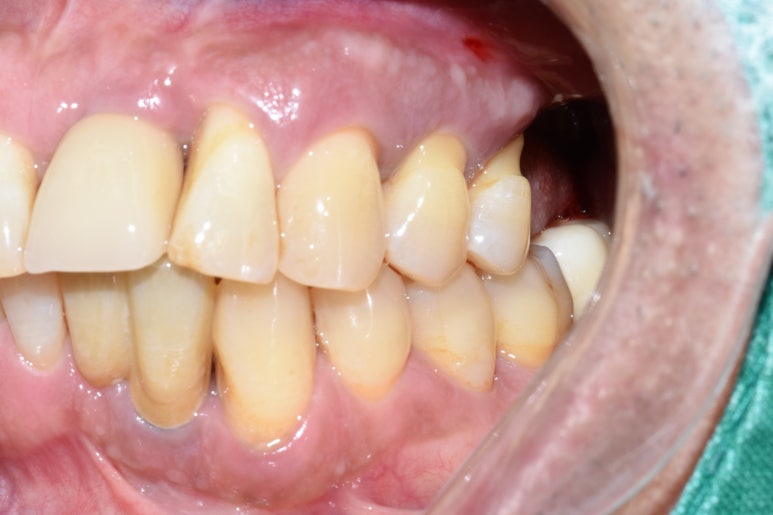

그래서 임플란트 픽스쳐를 제거하고,

옆의 흔들리는 치아 하나 까지 발치하여

임플란트 재수술은 임플란트 2개를 심고 머리 3개를 만들어 완성하였습니다.

전